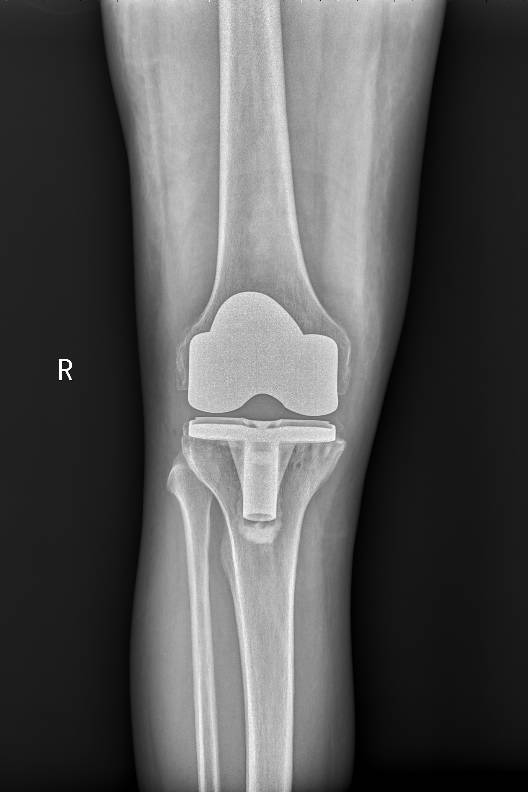

2020年1月初,程珂琳副主任醫師在門診見到了老Tim,看到他一瘸一拐艱難地走進診室,程醫生發現老Tim的病情比想象中還要嚴重。經過認真地詢問病史、查體,結合影像檢查,老Tim被確診為老年性雙膝骨性關節炎,程醫生表示可以通過手術有效緩解疼痛,并且配合術后的康復治療,患者能恢復正常行走。完善了相關檢查以后,1月10日,老Tim住進了關節骨病科,并于次日接受了手術治療。手術由關節骨病科、麻醉科等科室共同完成,程珂琳副主任醫師及其團隊僅用1個小時就成功地為老Tim實施了人工膝關節表面置換術,手術快而精準。

術前

術后